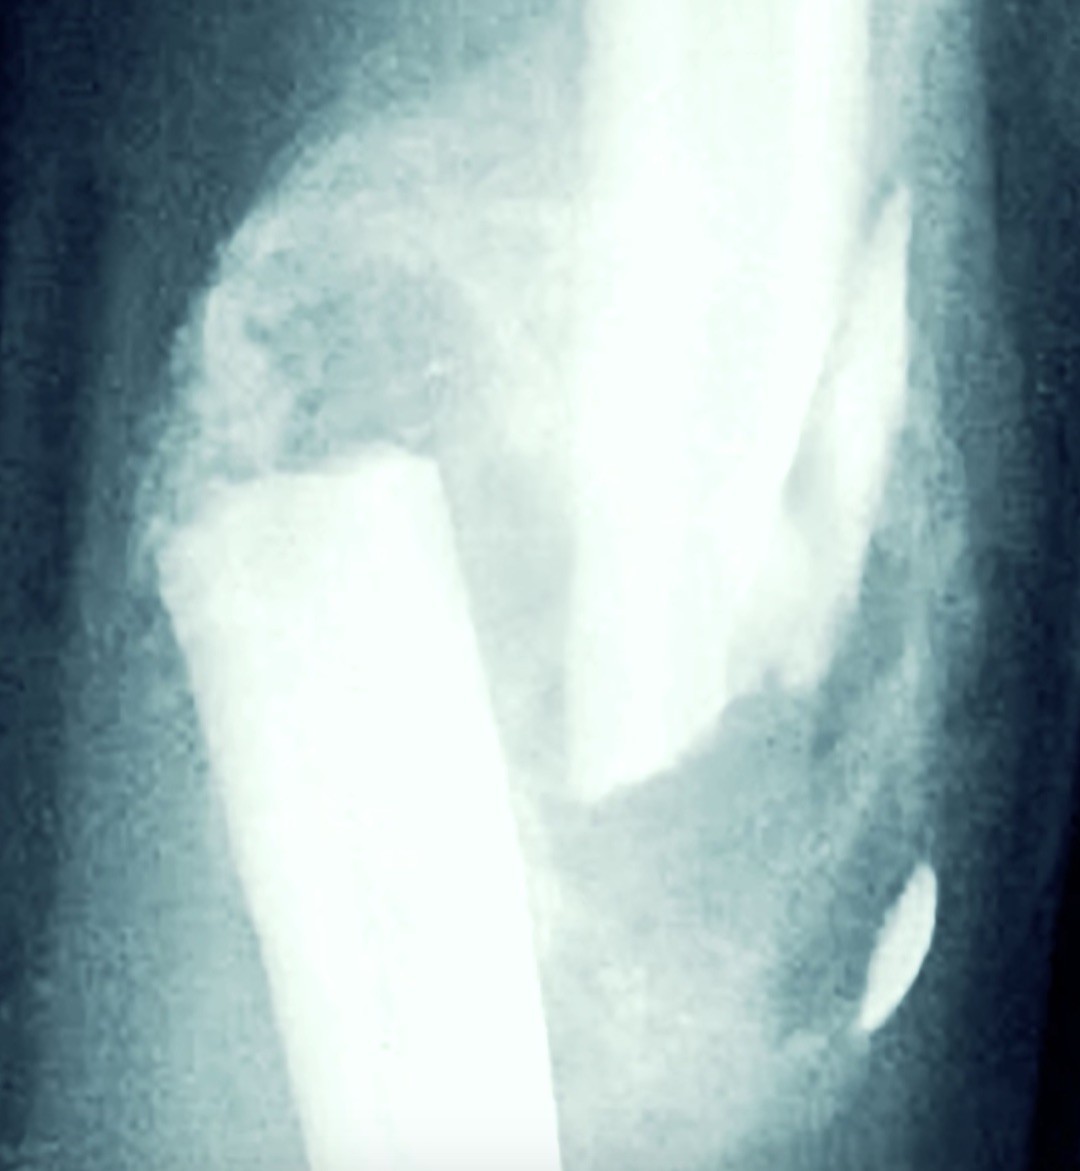

הטיפול בשבר ברגל הוא בגבס ובשבר מורכב במסמור תוך-לשדי וניתוח הוצאת מתכות אחרי זמן מה. אורתופדים מקבלים החלטה אם לנתח על פי מידת הפציעה, הבריאות הכללית ויכולת ההחלמה ללא ניתוח.

שבר ברגל המלוּוה בתזוזה של העצם, ולעיתים אף בעיוות (דפורמציה), מקנה לרוב אחוזי נכות גבוהים יותר. גם שבר מרוסק,  או שברים באזורים רגישים כגון המפרקים – אגן, קרסול או ברך – עשויים להוביל לנכות משמעותית, בשל המורכבות האנטומית וההשפעה הישירה על תפקוד איברים סמוכים. התזוזה של חלקי העצם תגרום אולי ליישור לא תקין של הרגל. המצב הזה שעלול להותיר מגבלה תפקודית קבועה ולהשפיע באופן ישיר על היקף הפיצוי בתביעה. קרא עוד על שבר עם תזוזה.

״שבר עם תזוזה לצד עיוות (דפורמציה) שווה אחוזי נכות גבוהים יותר״.